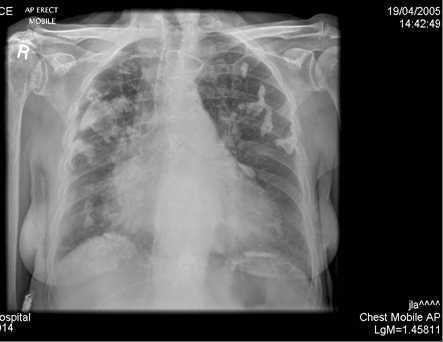

Pleural calcifications